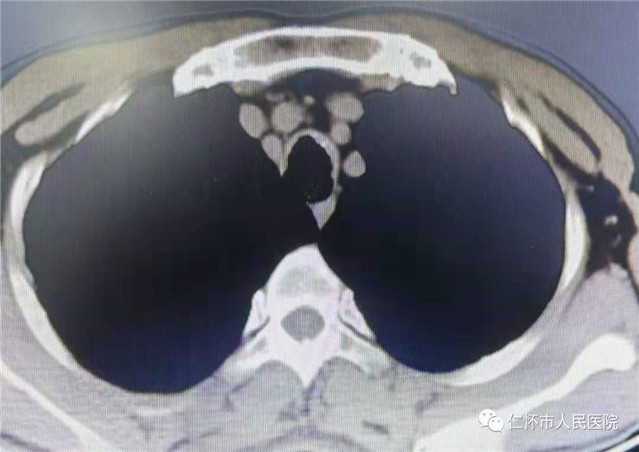

近日,我院呼吸与危重症医学科收治了一位中年男性患者,母××,44岁,该患者因“反复咳嗽、咳痰2月”入院。行胸部CT发现右肺中叶、双肺下叶多发小斑片状密度增高影,气管壁多发结节状影,考虑双肺感染,气管壁多发结节。入院后予积极抗感染及止咳对症治疗,针对患者气管壁多发结节,拟完善支气管镜检查明确病因。

影像学表现

胸部X线以及普通的厚层CT对本病不敏感。薄层CT对气管、支气管壁结节内的钙化影相当敏感。气管、主支气管内多发的黏膜下小结节钙化影并突向管腔是TO较具特征性的CT表现。结节直径通常为1—10mm,位于气管和主支气管的前壁和侧壁,无蒂或有蒂,可散发或融合成片,质硬,触之易出血,黏膜可正常、充血、灰白、小血管显露或呈粉红色钟乳石样,管腔可变窄或不规则,后壁(气管膜部)极少受累,声门及声门以上组织、叶支气管及其远端支气管也很少受累。